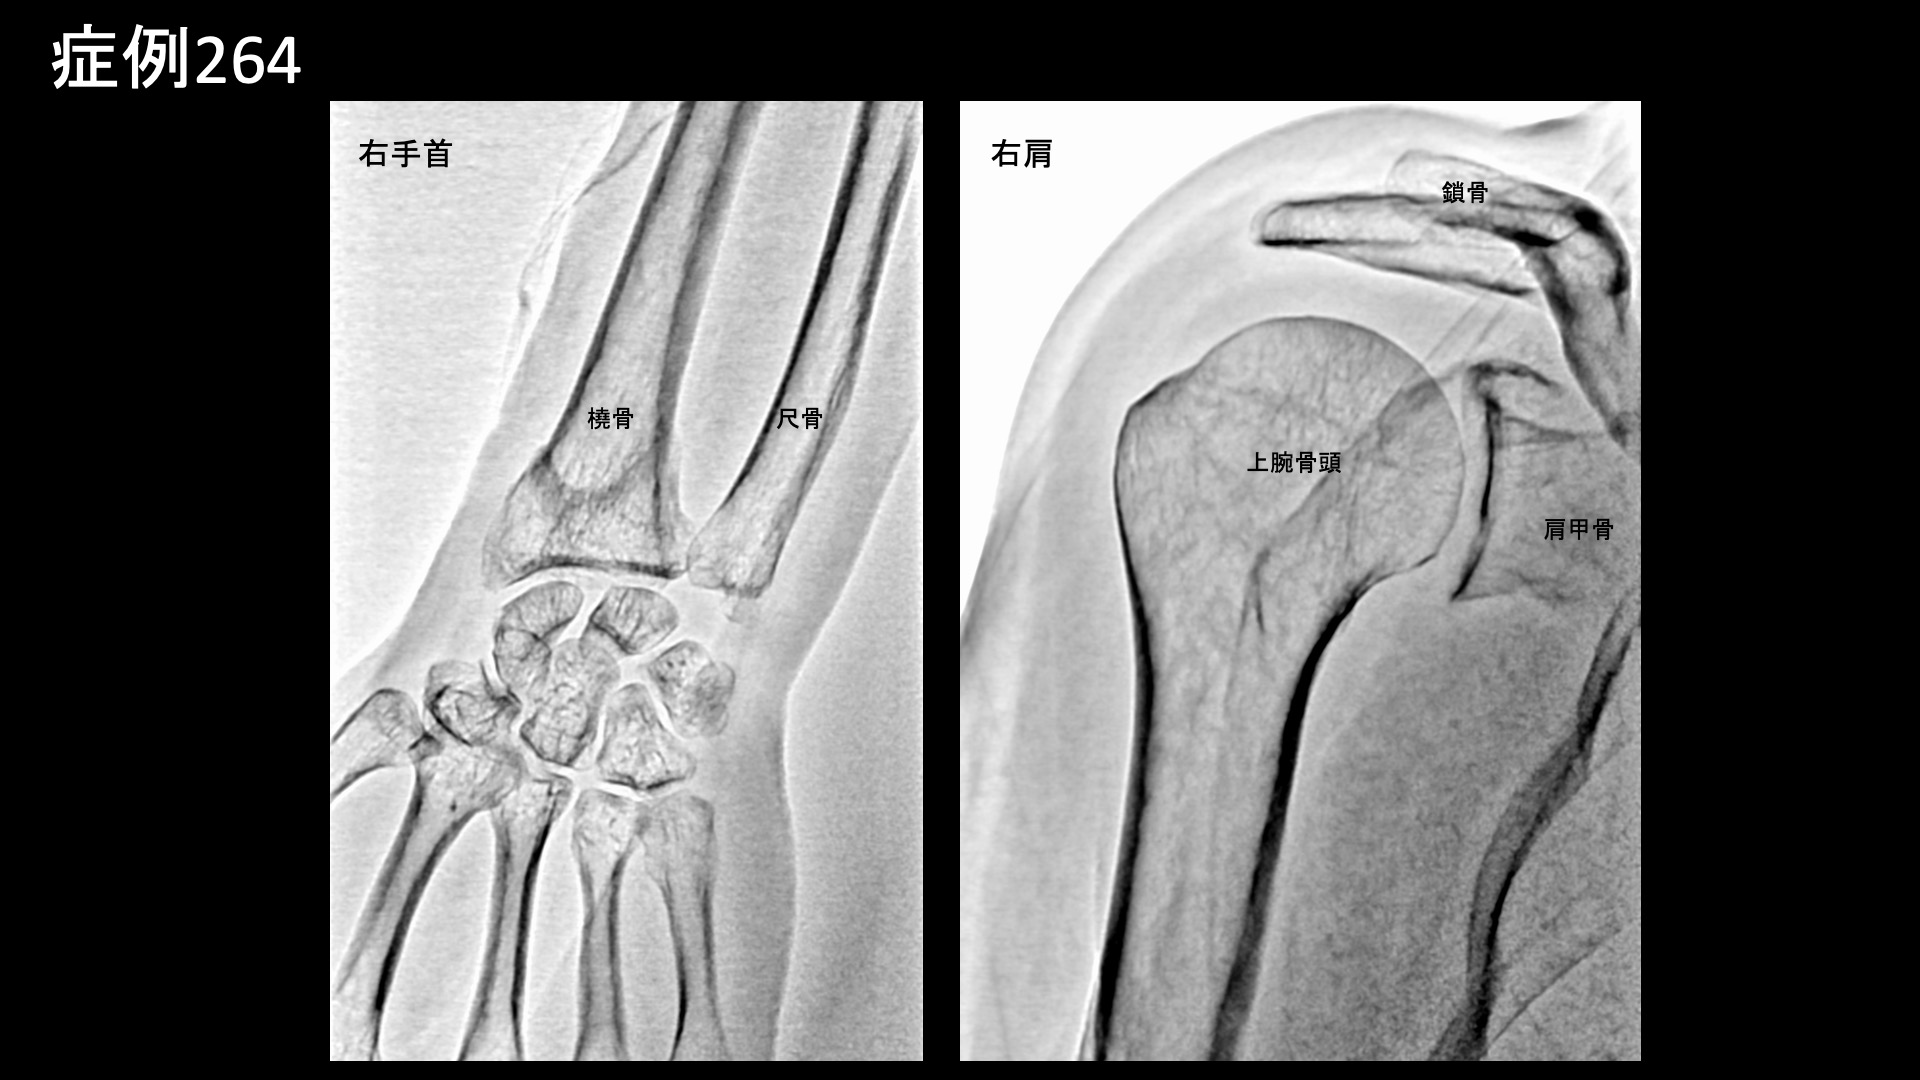

手:ばね指など 【50代:女性】骨折(橈骨遠位端骨折)治癒後も手首の小指側が痛い・・TFCC損傷および腱鞘炎に対するモヤモヤ血管治療(外傷後疼痛、橈骨遠位端骨折、TFCC損傷、尺側手根伸筋腱腱鞘炎) 2026.02.20 鴨井院長による動画解説 受診までの経過 4ヶ月前にバレーボールで手をついた際に右橈骨遠位端骨折を起こし、2ヶ月半くらいで治療が終了しましたが、その後特にきっかけなく右手首の小指側に痛みが出るようになりました。整骨院では骨折による拘縮が原因かもしれないと言われ、週2回の通院を続けましたが痛みが改善しませんでした。根本的なものを治したいと思い当院を受診されました。2ヶ月前からは五十肩も合併しており、併せて治療を希望されました。 診察時の所見 疼痛部位の特徴や、受傷機転からはTFCC損傷が疑われました。エコー検査では小指側の腱鞘炎(尺側手根伸筋腱の腱鞘炎)も合併していることが分かりました。右肩関節は自覚されていたとおり五十肩(凍結肩)で間違いありませんでしたが、比較的早期であり夜間痛は伴っておらず、動作時の痛みが主体でした。いずれも治療適応と判断し、モヤモヤ血管(病的新生血管)に対する運動器カテーテル治療(微細動脈塞栓術)を受けていただきました。 治療の所見 まず肩関節の治療を行いました。血管造影を行うと、肩関節では肩甲上動脈、烏口枝などでモヤモヤ血管が濃染像として描出されました。治療後は画像上速やかに消失しました。その他複数箇所の治療を行い終了しました。続いて右手首の治療です。TFCC損傷の主要責任血管である骨間動脈で同様にモヤモヤ血管が豊富に描出されました。骨折後でしたので、その分より多く認められたのかもしれません。両方合わせて25分程度で治療を終了しました。 治療前画像:損傷を受ける、あるいは繰り返しのストレスにより発生した異常な新生血管 治療後画像:カテーテルを用いて塞栓物質を血管内に投与し新生血管を塞いだ状態 治療費用:治療する部位によって費用が異なりますのでこちらをご参照ください。 主なリスク・副作用等:針を刺した場所が出血により腫れや痛みを生じたり、感染したりすることがあります(穿刺部合併症)。造影剤によるアレルギー(皮膚のかゆみ・赤み・息苦しくなるなどの症状)が出ることがあります。 治療後の経過 治療後、右肩は1週間経たないうちに楽になり9割程度の痛みが改善されました。動きも良くなりました。治療後2週間、右手首も術前の痛みの半分以下となりました。まだ違和感は残っており、力がまだ十分入れられませんでした。非常に経過良好でしたので、しばらく間隔を空けて治療後2ヶ月半で再診としました。右肩は引き続き順調にほとんど痛みはありませんでした。右手首も日常生活では問題なく、スポーツ復帰も果たせていました。まだスポーツの後には少し痛みが出ました。手首の背屈や回内回外動作では異常なく、エコー検査でも問題ありませんでしたので終診としています。残存症状については、安静による自然軽快が見込まれます。 TFCC損傷は局所の酷使により時間をかけて形成されることが多く、今回の受傷時に一気に悪くしてしまった可能性があります。カテーテル治療後の経過としては、すぐにカラッと良くなるというよりは、1ヶ月半くらいまでの間に、大幅に改善され、しばらく一定の少しの痛みや違和感が持続し、時間経過とともに改善されていくことが多いです。一方、スポーツなどが原因であることが多く、痛みがある程度良くなると完治していない状態でも早期から復帰したり、治療中もプレーし続けたりする方は少なくありません。酷使を続けると、良くなるのに時間がかかったり、多少の再発をしたりということもあります。治療後、少なくとも1ヶ月程度は酷使しないことが重要です。尚、実際にはただ炎症が起きているだけではなく損傷しているため、その重症度には個人差があります。正確に評価するためにはMRI検査が必要ですが、一般的にはほとんどの場合で保存的治療方針となります。モヤモヤ血管治療は非常に有力な治療選択肢ですが、本症例では骨折後遺症や腱鞘炎についても同時に治療できており、より意義が大きかったものと思われます。 TFCC損傷の詳細はこちら 【50代:女性】顔面に生じた難治の痺れと痛み、顔面骨折に三叉神経第2枝損傷を合併した外傷後疼痛に対するモヤモヤ血管治療(外傷後疼痛、顔面骨折、三叉神経第2枝損傷) 前の記事 【50代:女性】首がきしみ、肩はガチガチ、頭が重く、顎はカクカク・・2回のカテーテル治療により改善した重症首肩こりおよび頭痛・顎関節症(詳細説明あり)(首肩こり、頸肩腕症候群、頭痛、顎関節症、食いしばり(ブラキシズム)) 次の記事